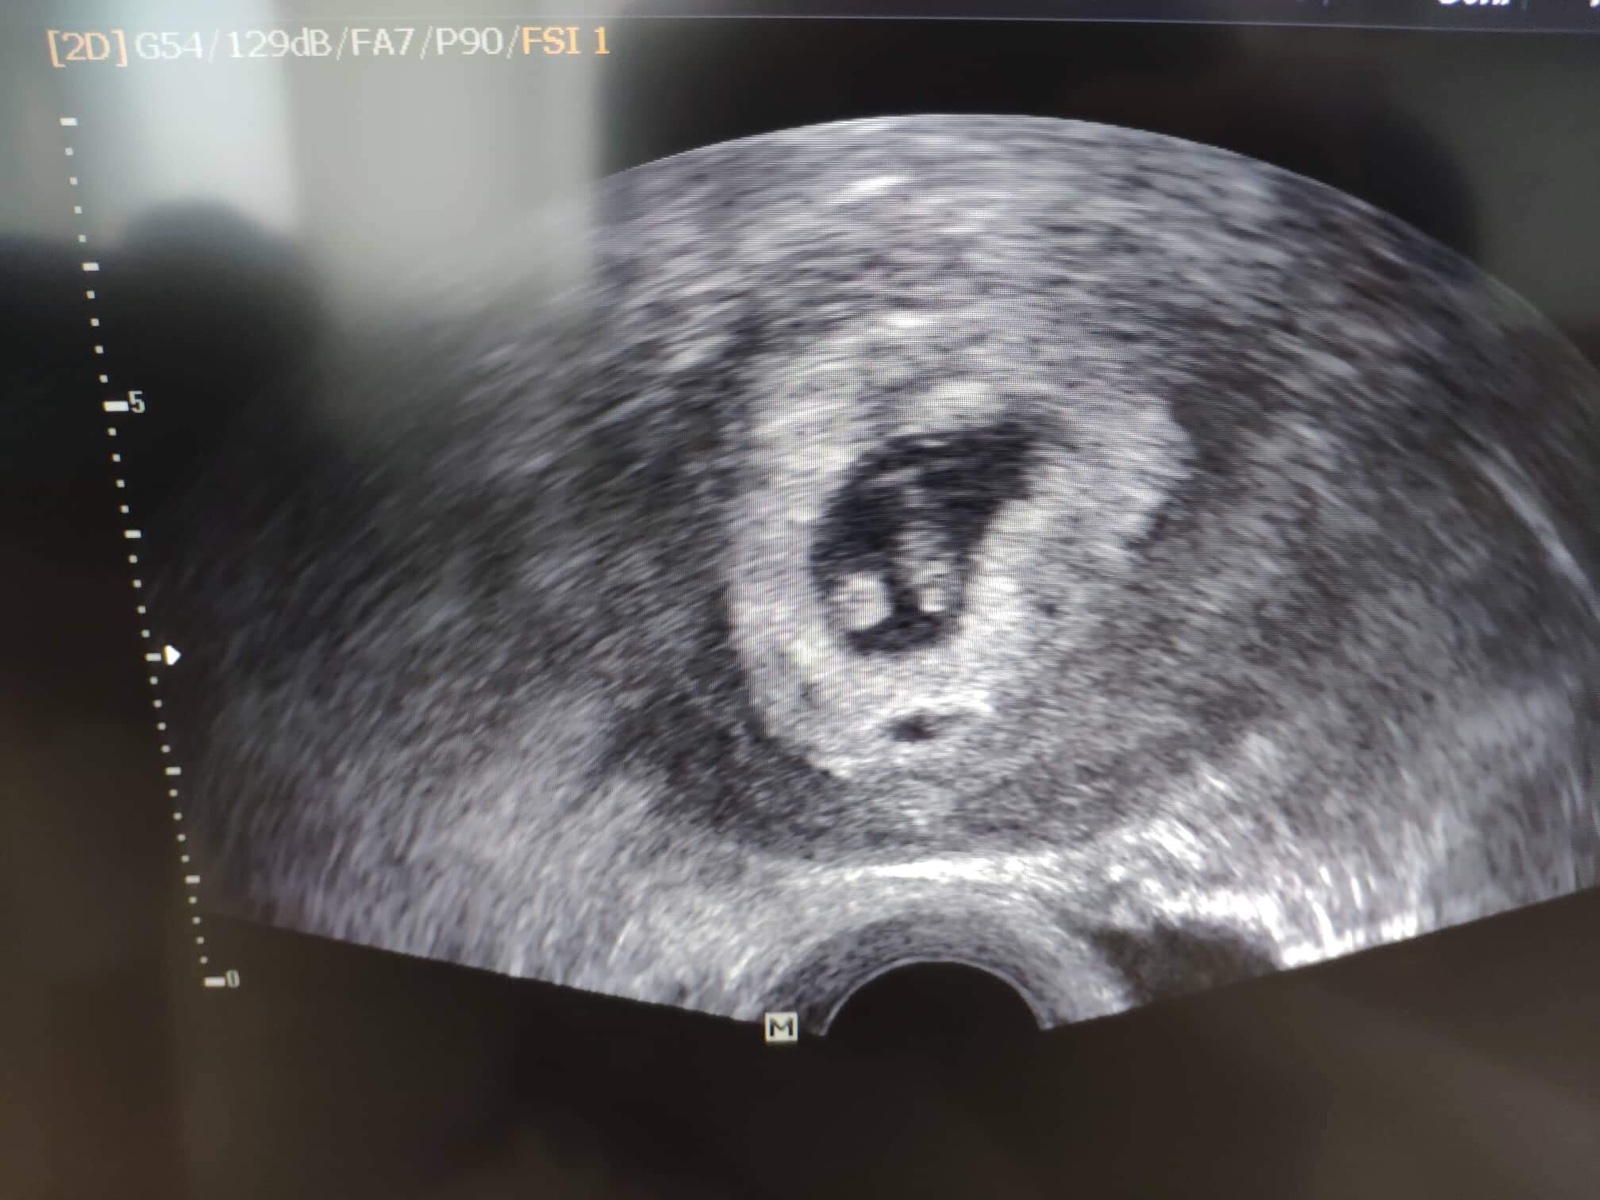

@lucik253 ahoj v kolikatem jsi tydnu? Me rekla v 5+2 ze nema srdecni akci a ze v patek revize a ze je velke do 5tydne...tak se ptam kdy jsi mela viditelne srdicko?dekuju moc za odpoved ...jsem trosku nadne😢bojim se ze opravdu pujdu na revizi...

@racochejlek87 ahoj v 5+2 ještě nejde videt srdeční činnost, mě šla vidět taky později. Sám doktor říkal že 5tt je brzy na srdíčko

@racochejlek87 To je strašně brzy hnát na revizi, určitě bych počkala, to je dobře, že jdeš i jinam!! Já jsem měla vidět srdíčko v 6+5, to mělo embryjko 6mm. Moc držím palce a věřím, že se ukáže.🙏🏻🍀